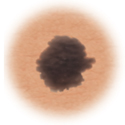

Melanoma

Sign

Characteristic

Skin cancer showing asymmetry.

Asymmetry

When half of the mole does not match the other half

Skin cancer showing more than one color.

Color

When the color of the mole varies throughout